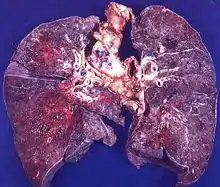

- Пневмомикоз — заболевание лёгких с их поражением грибковой инфекцией любой этиологии (чаще облигатно-патогенными и факультативно-патогенными грибками, оомицетами, аскомицетами, несовершенными грибами)[7].